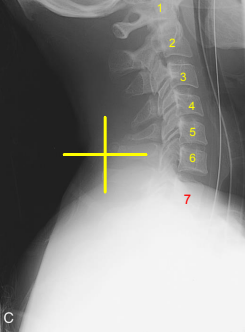

Lateral C-Spine: Eval Criteria

Cervical vertebral bodies, intervertebral joint spaces, articular pillars, spinous processes, and zygapophyseal joints demoed

C1 through C7-T1 intervertebral joint spaces are clearly seen

R and L articular pillars and zygapophyseal joints should be superimposed for each vertebra

Bodies free of superimposition of the articular pillars

Spinous process seen in profile

Lateral C-Spine: Is this Image Good?

No

C7 is obscured

C1 anatomy is clipped and spine is not centered

Need to center higher and more anterior

Tilt leads to poor superimposition of zygapophyseal joints

Used AEC but it wasn’t centered to bone (underexposed)